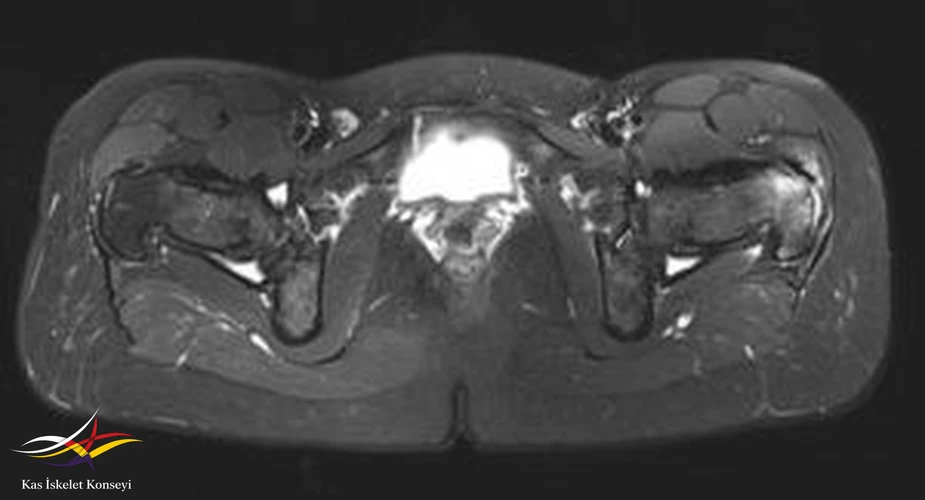

İncelemeler: Kalça MRG ve BT incelemelerinde sol femur trokanter major bölgesinde kemik iliği ödemi, bilateral şüpheli trokanterik bölge fraktür hattı, trokanterik bursit ile uyumlu görünüm saptandı.

Resim 3. Aksiyal T2 ağırlıklı MRG incelemesi.